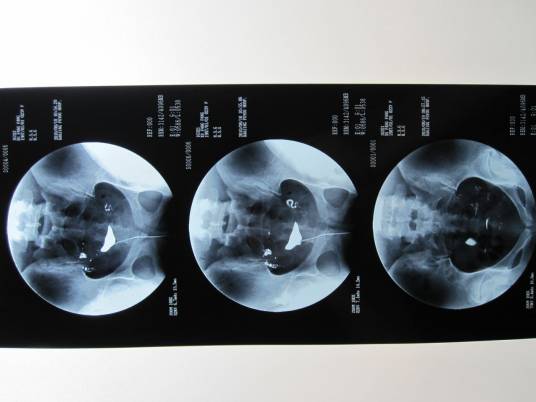

碘油造影是以碘化油为造影剂所进行的经X线的子宫输卵管造影。输卵管碘油造影是通过导管向宫腔及输卵管注入碘化油造影剂,利用X线诊断仪行X线透视及摄片,根据造影剂在输卵管及盆腔内的显影情况来了解输卵管是否通畅、阻塞部位及宫腔形态的一种检查方法。

该检查损伤小,在有经验的医验操作下并附以数字X光机的应用能对输卵管堵塞作出正确诊断,准确率达98%,且具有一定的治疗作用,是用来了解输卵管是否通畅及通畅的程度和具体堵塞部位的最常用的检查方法。

(3)若应用金属导管将造影剂充满导管,排尽空气,而后将导管插入子宫颈,堵紧宫颈外口,不至使造影剂外溢,在X线透视下观察造影剂流经宫腔及输卵管情况并摄片。在这个时期最好要摄片两张,第一张掌握在造影剂充满子宫及输卵管全程的时候,造影剂经输卵管进入盆腔内一少部分时摄第二张,如造影剂进入盆腔内弥散过多拍第二张,由于造影剂进入盆腔内弥散将影响对输卵管具体情况的准确观察,而后再次注入一定量的造影剂,顺便拔出导管后让患者适当走动,24小时左右待造影剂在盆腔内充分弥散时拍最后一张延迟造影片。若应用气囊导管进行造影其过程和金属导管造影过程大体相同。须要注意的是在进行子宫输卵管碘油造影检查过程的拍片的抓拍时机,一定要掌握在造影剂流经输卵管,保持一定压力在造影剂流动的过程中拍片,只有这样才能清楚的了解管腔的具体通畅情况。

合格的造影是诊断的第一步,而明确的诊断却是治疗的关键,同一张片子不同的医生由于经验的不同会得出不同的结论,下面我们来看一些常见的片子。

1, 正常的子宫输卵管碘油造影片子

1.输卵管通畅

2.输卵管阻塞

3.输卵管通而不畅